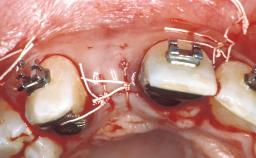

In February 2005, a 25-year-old female patient, a nonsmoker, was referred to our clinic due to tooth 11 presenting a chronic fistula following unsuccessful root-canal treatment and several attempts at endodontic surgery. The dental history revealed that more than ten years earlier, teeth 11 and 21 had been traumatized during a sports accident. Consequently, 11 had lost its vitality, and there were two moderate fractures of the mesioincisal borders of the two central incisors that had been restored with direct composite restorations. At the time of examination, the composite restorations showed signs of wear, some discoloration, and marginal infiltration. The patient also complained about a moderate discoloration of the clinical crown of the non-vital tooth 11. The patient was in good general health, and her medical history revealed no significant findings.